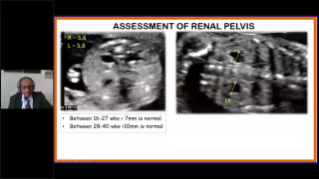

Geburtshilfe